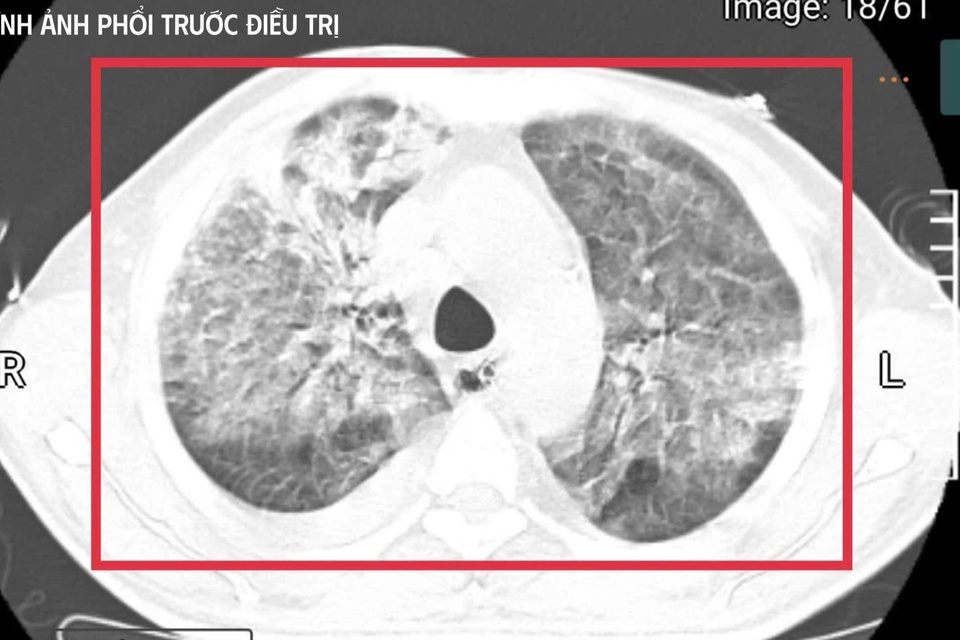

Bệnh nhân 35 tuổi từ vùng lưu hành vi khuẩn mang bệnh Whitmore trở về trong tình trạng nguy kịch, sốc nhiễm khuẩn, suy đa tạng, thân nhiệt hơn 41°C và hôn mê sâu.

Bệnh nhân nam L.V.T. (35 tuổi, quê Nghệ An) sinh sống và làm việc tại Thái Lan - khu vực lưu hành bệnh Whitmore cao. Anh có tiền sử đái tháo đường mới phát hiện. Khoảng 5 tuần trước khi về Việt Nam, người đàn ông xuất hiện sốt cao liên tục, khó thở, kích thích nhiều, phải nhập cấp cứu tại một cơ sở y tế ở Thái Lan.

Tại đây, bệnh nhân được đặt nội khí quản thở máy; kết quả cấy máu xác định nhiễm Burkholderia pseudomallei - tác nhân gây bệnh Whitmore. Dù được điều trị ban đầu, tình trạng vẫn diễn tiến nặng nên gia đình xin chuyển về Việt Nam để tiếp tục điều trị. Nhưng chỉ sau ít ngày, người đàn ông này rơi vào sốc nhiễm khuẩn, suy đa tạng, sốt cao liên tục, rối loạn ý thức và được chuyển gấp ra khoa Cấp cứu, Bệnh viện Bệnh Nhiệt đới Trung ương (Hà Nội).

Thạc sĩ, bác sĩ nội trú Nguyễn Kim Anh, khoa Cấp cứu, cho biết thời điểm tiếp nhận người bệnh là "khoảnh khắc rất căng thẳng". Bệnh nhân hôn mê sâu, thang điểm Glasgow chỉ còn 9, mất phản xạ đường thở, phụ thuộc hoàn toàn vào máy thở. Nhiệt độ liên tục 41-42°C kèm run cơ toàn thân, gợi ý tình trạng tăng thân nhiệt ác tính trên nền nhiễm khuẩn huyết tối cấp.

Xét nghiệm cho thấy men gan và bilirubin của anh T. tăng cao, rối loạn đông máu, creatinin tăng nhanh kèm vô niệu - biểu hiện của suy gan, suy thận cấp tiến triển. Nồng độ CK vượt quá 100.000 U/l, kèm đau cơ và nước tiểu sẫm màu, phù hợp với tiêu cơ vân cấp.

Không chỉ vậy, các chỉ số viêm như CRP, PCT tăng rất cao, phản ánh tình trạng nhiễm trùng, nhiễm độc toàn thân dữ dội. Trên nền đó là đái tháo đường chưa kiểm soát và viêm gan C mạn, khiến cơ thể người bệnh càng suy sụp.